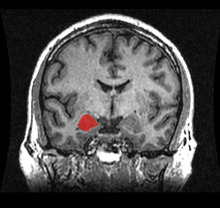

MRI Location amygdala

Focal seizures in the temporal lobe involve small areas of the lobe such as the amygdala and hippocampus.